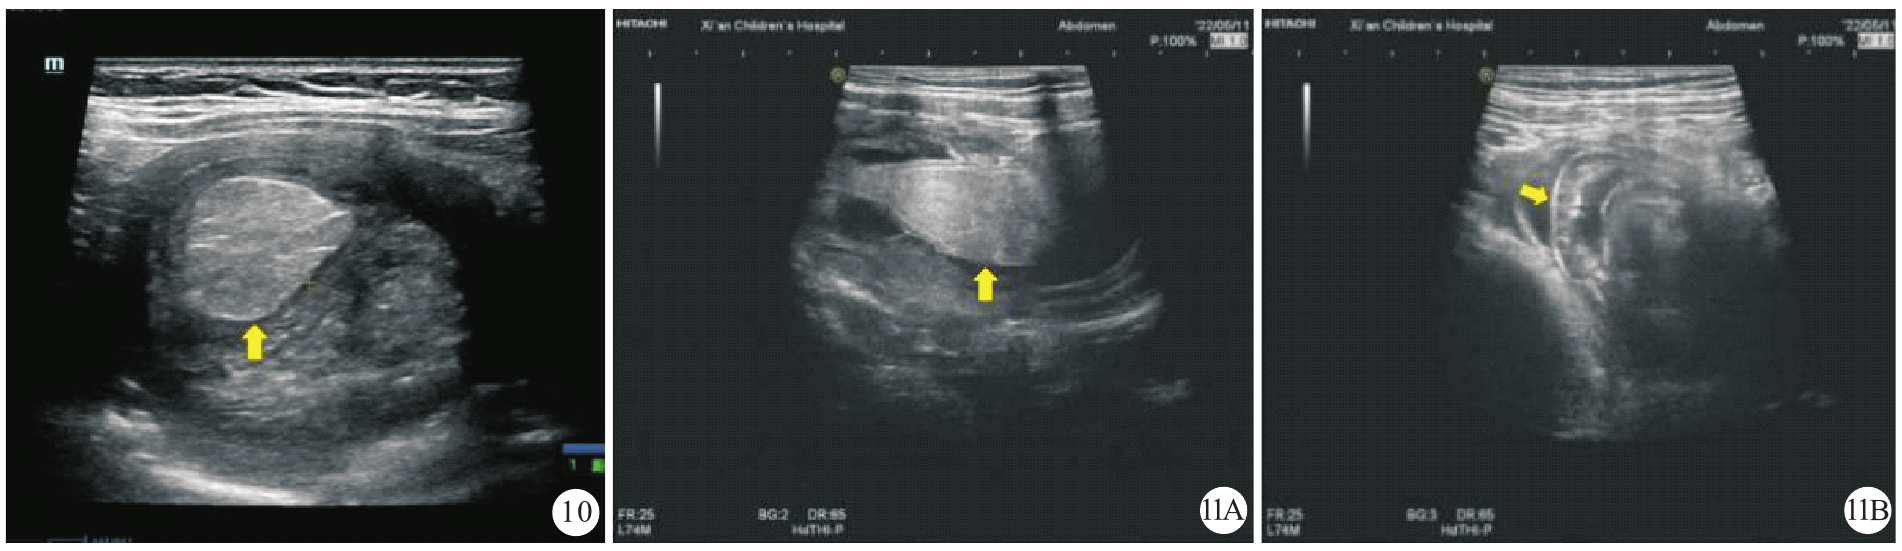

图11 梅克尔憩室内翻继发性肠套叠误诊为变态反应性紫癜继发性肠套叠患儿(女性,12岁2个月)的超声声像图[图11A:纵断面示憩室内翻(黄色箭头所示),中央区高回声与系膜相延续;图11B:横断面示套筒内肠壁水肿增厚(黄色箭头所示),加之患儿有变态反应性紫癜病史,故被误诊为变态反应性紫癜继发肠套叠]